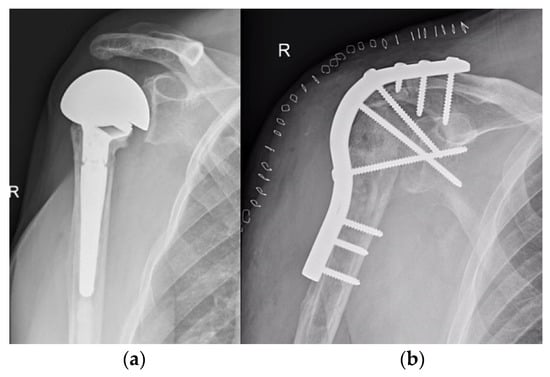

5.2. Shoulder

- Mattei, L.; Mortera, S.; Arrigoni, C.; Castoldi, F. Anatomic Shoulder Arthroplasty: An Update on Indications, Technique, Results and Complication Rates. Joints 2015, 3, 72–77. [Google Scholar] [CrossRef]

- van den Bekerom, M.P.J.; Geervliet, P.C.; Somford, M.P.; van den Borne, M.P.J.; Boer, R. Total Shoulder Arthroplasty versus Hemiarthroplasty for Glenohumeral Arthritis: A Systematic Review of the Literature at Long-Term Follow-Up. Int. J. Shoulder Surg. 2013, 7, 110–115. [Google Scholar] [CrossRef] [PubMed]

- Trofa, D.; Rajaee, S.S.; Smith, E.L. Nationwide Trends in Total Shoulder Arthroplasty and Hemiarthroplasty for Osteoarthritis. Am. J. Orthop. 2014, 43, 166–172. [Google Scholar] [PubMed]

- Zhang, B.; Chen, G.; Fan, T.; Chen, Z. Resurfacing Hemiarthroplasty versus Stemmed Hemiarthroplasty for Glenohumeral Osteoarthritis: A Meta-Analysis. Arthroplasty 2020, 2, 25. [Google Scholar] [CrossRef] [PubMed]